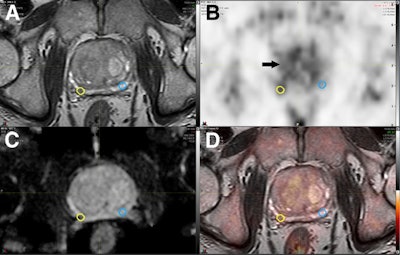

The researchers analyzed 56 patients who underwent 3-tesla MRI scans of the pelvis (Ingenia, Philips Healthcare) with a protocol that included axial 2D and 3D T2-weighted fast spin-echo imaging, axial diffusion-weighted imaging, and axial T1-weighted unenhanced and dynamic contrast-enhanced MRI. Images were prospectively classified on the five-point Likert scale, with a score of 1 indicating a negative result for cancer and 5 as positive for cancer. Likert scores of 1 and 2 were not referred for a biopsy, while scores of 3, 4, and 5 were targeted for follow-up biopsy.

The subjects also underwent choline-PET/CT imaging (Biograph TrueV mCT, Siemens Healthineers), with the PET portion scanning the lower abdomen and pelvis 20 minutes after injection of 230 (± 31 MBq) of choline. A choline tumor-to-background ratio (TBR) of 1.58 or greater was a positive indication for cancer.

The researchers then analyzed several choline-PET/mpMRI models and found the most effective approach for prostate cancer detection was to combine low- (Likert 3), intermediate- (Likert 4), and high-risk (Likert 5) mpMRI results with an elevated choline TBR greater than 1.58 as positive for significant cancer.

This combination increased accuracy on a per-lesion basis significantly to 89% (p < 0.001). In fact, the choline TBR threshold of 1.58 significantly improved the diagnostic accuracy over the mpMRI on a per-patient basis, as well, from 87% to 93% (p < 0.001).